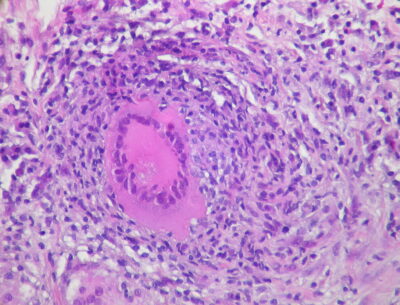

MTB typically affects the lungs (pulmonary TB) but frequently also involves other extrapulmonary sites. Intrathoracic tuberculosis is defined by involvement of either the lung parenchyma (infiltrates, cavities, miliary disease), the pleural space, or intrathoracic (hilar, mediastinal) lymph nodes.14 In pulmonary MTB, the bacteria enter the body via inhalation and colonize terminal alveoli.15 The presence of MTB activates the host immune response, stimulating the migration of macrophages and lymphocytes to the infection site. These immune cells commence granuloma formation as a component of the inflammatory response. (See Figure 1.) However, it is within these granulomas that MTB can persist in a latent stage for months to decades. Changes in host immune status can cause latent infection to become active.16 The balance between bacterial pathogenicity and the strength of the host immune system determines the clinical presentation of TB disease. This balance is influenced by several factors, including the initial infectious dose of MTB, the virulence of the pathogen, and overall host health and the presence of comorbid diseases (e.g., HIV/AIDS or diabetes).11

Figure 1. Pulmonary Tuberculosis

Source: Rosen Y. Pulmonary tuberculosis — non-necrotizing granuloma. Published Dec. 20, 2011. https://commons.wikimedia.org/wiki/File:Pulmonary_tuberculosis_-_Non-necrotizing_granuloma_(6545183785).jpg